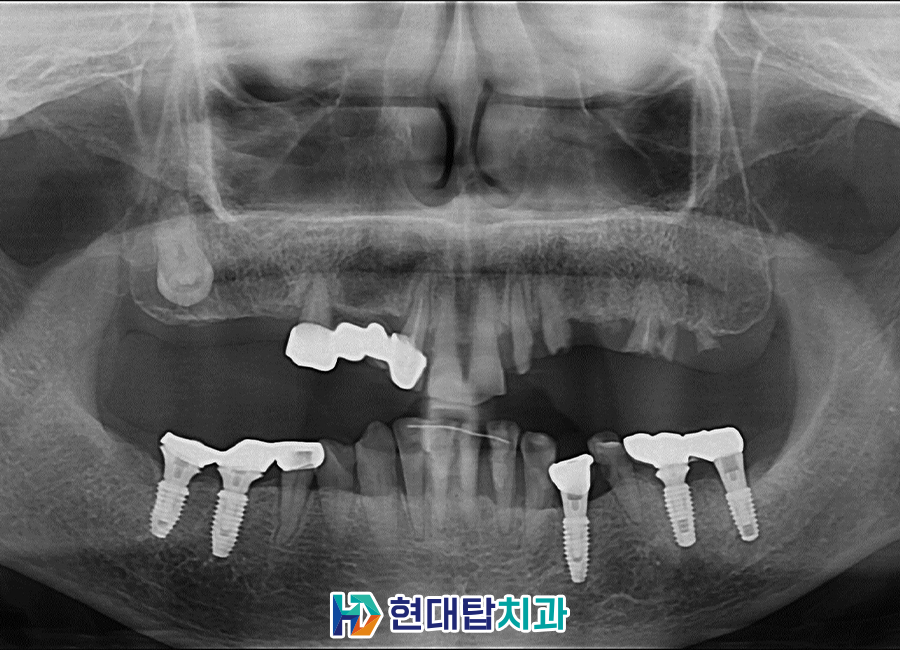

환자분께서는 오른쪽 위 어금니

부위는 이미 상실한 상태였고,

왼쪽 위는 앞니를 제외하고

남아 있는 치아들은 치아머리가

부러져 뿌리만 남아 있는 상태였습니다.

하여 살려서 사용할 수 없는

왼쪽 위의 치아 뿌리들을 모두

발치하고, 오른쪽에 남아 있던 브릿지까지

모두 발치한 후 치아 상실 부위에

임플란트 식립 계획을 수립하였습니다.

오른쪽 아래 기존 임플란트의

보철물을 위쪽 임플란트와 잘

맞도록 수정하여 보다 안정적인

교합을 가질 수 있도록 하였습니다.